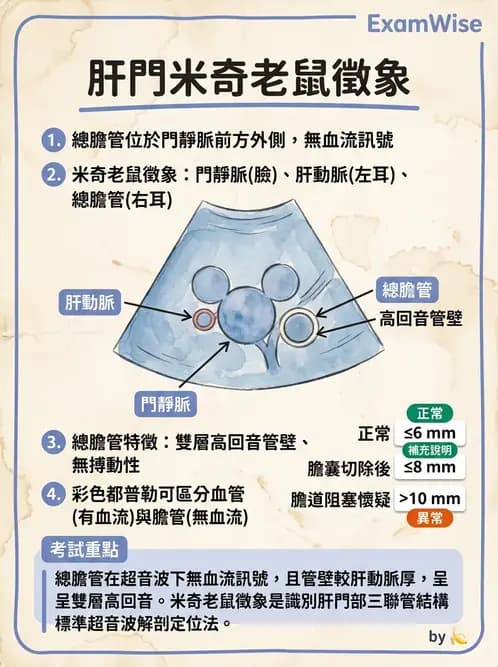

本題考查腹部超音波(abdominal ultrasound)對肝門部(porta hepatis)解剖結構的辨識,特別是「米奇老鼠徵象(Mickey Mouse sign)」中三個管狀結構的鑑別——門靜脈(portal vein)、肝動脈(hepatic artery)與總膽管(common bile duct, CBD)。

此結構位於肝門部,鄰近一個較大的圓形無回音管狀結構(即門靜脈)。根據位置關係:

- 門靜脈(portal vein):最大的管狀無回音結構,位於後方中央(Mickey Mouse 臉部)

- 肝動脈(hepatic artery):門靜脈前方偏內側(左耳),較小,搏動性(需 Doppler 確認)

- 總膽管(common bile duct):門靜脈前方偏外側(右耳),較小,無血流,管壁較厚且呈高回音

箭頭所指之結構具有以下特徵:雙層高回音管壁、無回音內腔、無搏動性血流訊號,符合總膽管的